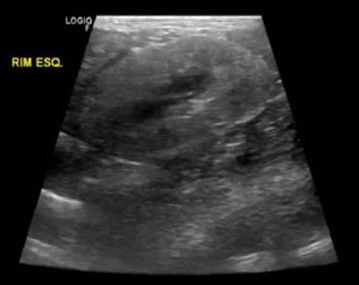

- ์ด์ํ ๊ฒ์ฌ

ํผ์ง, ์์ง ๊ฒฝ๊ณ๊ฐ ์์, hyperechoic